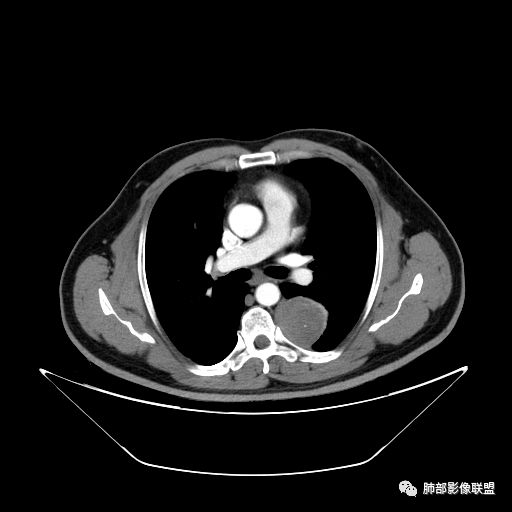

平安是福:平扫31Hu,动脉期33–42Hu,静脉期,39–54Hu。

3.降主动脉这一相对固定结构向前方推移,提示病灶相对坚实且有牢固附着点,不支持来自柔软的肺组织。

4.可疑肋间动脉病供血,提示肿块来自后纵隔的可能性。

7.静脉期轻度强化,注意不是环形强化,亦未显示明确的“AB区”,神经鞘瘤与副节瘤亦未找到支持点。